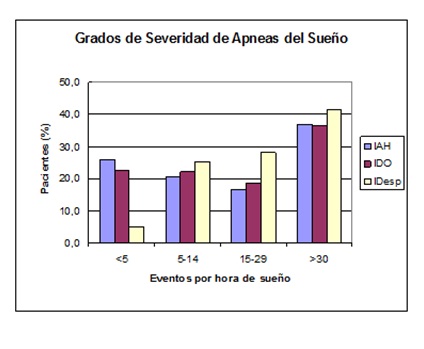

Se estudiaron por síndrome clínico de apneas-hipopneas obstructivas del sueño, 2310 de 2843 pacientes con trastornos respiratorios del sueño (81,3%). Se confirmó el diagnóstico (por el criterio de IAH > 5) en 1709 pacientes con síndrome clínico (74,0%). El restante 26,0% con IAH < 5, corresponde a resultados verdaderos negativos, o a las siguientes categorías diagnósticas no consideradas para este trabajo: síndrome de aumento de resistencia de la vía aérea superior durante el sueño (SARVS) y ronquido patológico. Los grados de severidad se evaluaron por el IAH, el IDO y el IDesp (Figura 12). En los pacientes con trastornos leves y severos por IAH, los tres índices generalmente coincidieron. En los grados moderados el Idesp fue mayor que el IAH y el IDO.

Figura 12: Distribución de los índices de severidad en estudios de pacientes con SAHOS. IAH: índice de apneas+hipopneas por hora de sueño; IDO: índice de desaturaciones > 3% de SpO2 por hora de sueño; IDesp: índice de micro-despertares por hora de sueño. Grado leve: IAH= 5 a 15; grado moderado: IAH = 15 a 30; grado severo IAH>30.